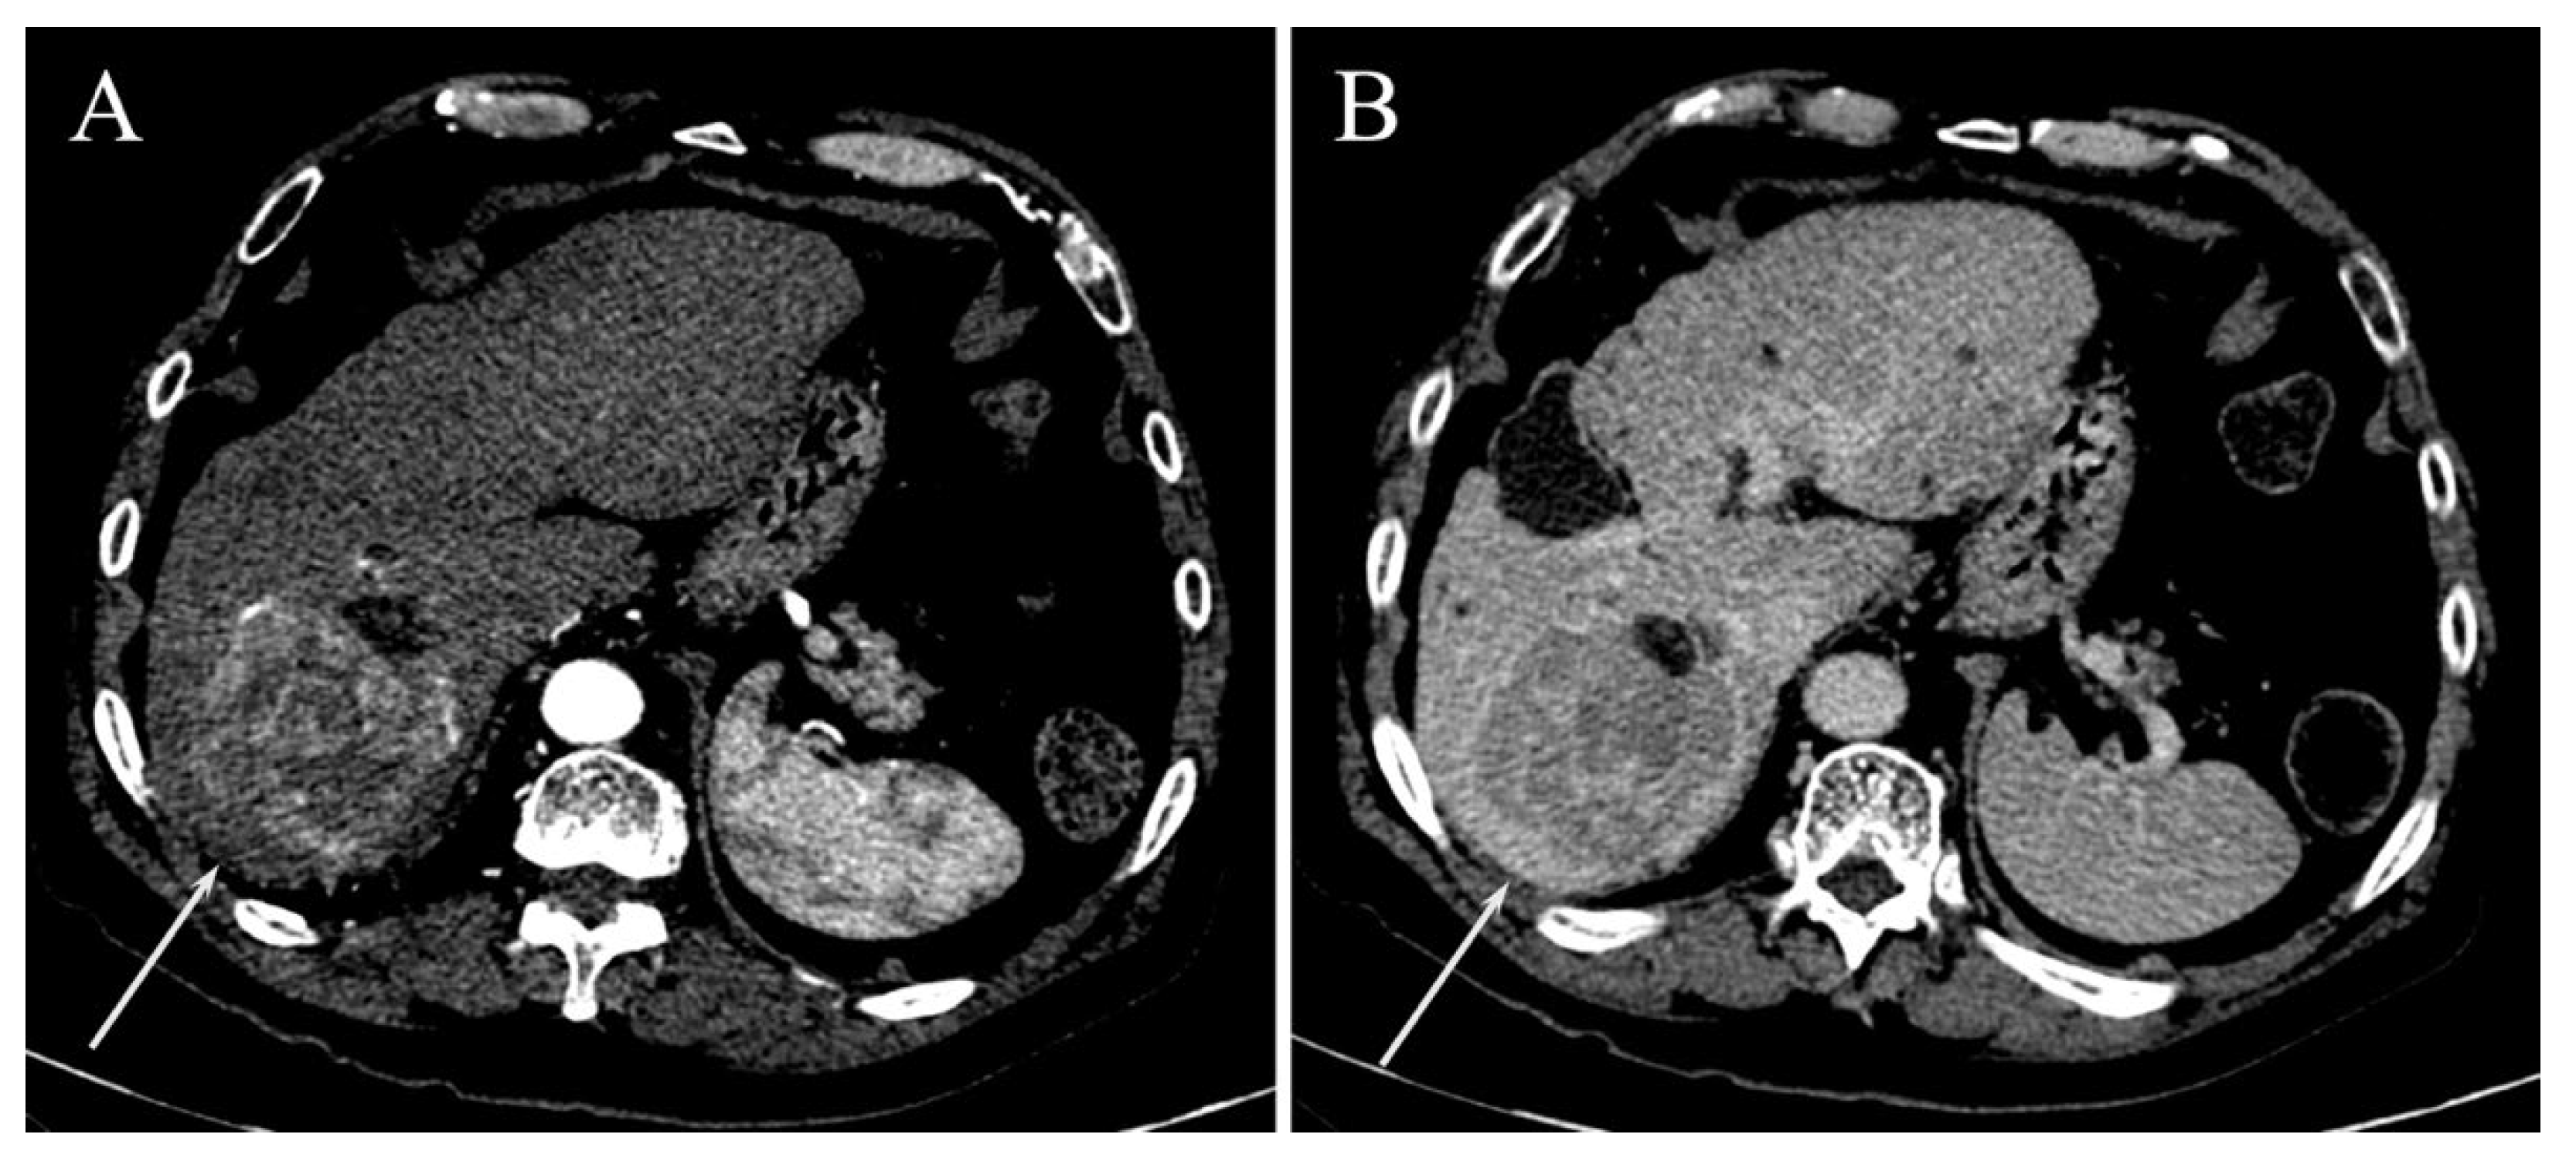

| TTPVI | 14 (38.9%) | 11 (20%) | 0.058 |